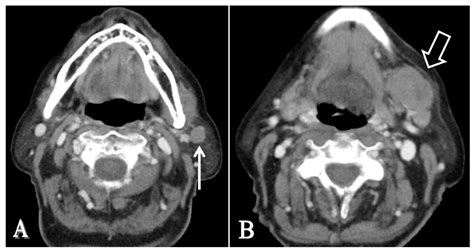

MRI/CT Scan See the neoplasm size and percolation into besiege tissues.